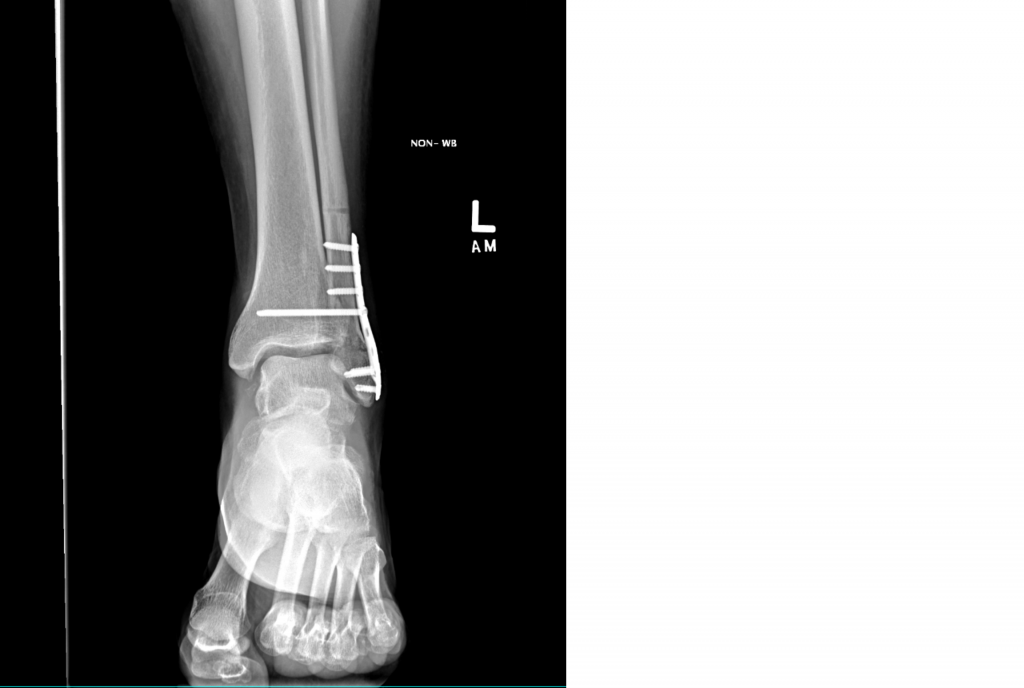

I broke my ankle, just slipping on the sidewalk on a rainy NYC day. I was x-rayed and was told to go to ER which was at NYP. A resident there set the bone and put it in a splint/cast. A few days later I went to Dr. Behrens' office and was told I needed surgery to bring the bones back together and hold them in place with a plate and screws.

Dr. Behrens and his PA Meagan Murtagh were thoroughly professional as were the nurses and radiology team at HSS. I was most happy to have an honest and open Q&A session with them. I agreed to the surgery. All went well and I was back in a new cast. About 5 weeks later the cast came off and I stayed off the ankle for another 2 weeks or so. I went back to Dr. Behrens and got another x-ray and I was pronounced as ready to walk with a cane. But that only lasted a couple of days and I was soon walking gingerly without the cane and recovering all the muscle strength and range of motion at PT sessions.

I went back a few months later and had another x-ray. This showed two things. The bone was healing well, and the largest screw, which traversed the ankle broke in two. But Dr. Behrens assured me that this is somewhat normal and in fact studies showed that patients who had the same thing happen did better over time. I then went back to my usual Yoga routine and walking around New York.